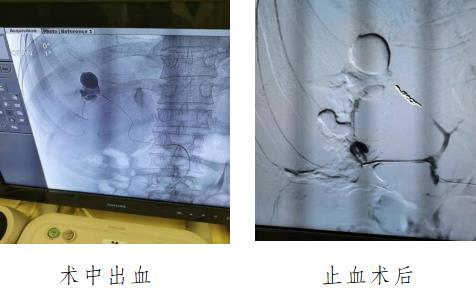

經(jīng)輸血2000多毫升,止血抗感染治療后,出血仍未能控制。外二科周雄主任組織全科骨干醫(yī)生進(jìn)行病例討論,還邀請(qǐng)了南方醫(yī)珠江醫(yī)院教授進(jìn)行遠(yuǎn)程會(huì)診。經(jīng)討論并取得患者及家屬同意決定對(duì)患者行DSA腎造影和介入性超選擇性腎血管栓塞止血。

經(jīng)過醫(yī)護(hù)人員努力,通過造影終于找到了腎裂傷三個(gè)大出血處,導(dǎo)線精準(zhǔn)入到腎的三級(jí)血管并及時(shí)止血。經(jīng)過輸血等積極治療,保住了患者的生命,還保住了患者唯一的腎。經(jīng)過一個(gè)月的精心治療及護(hù)理,患者順利康復(fù)出院,患者家屬非常感謝全科的醫(yī)護(hù)人員?;颊呖祻?fù)出院。